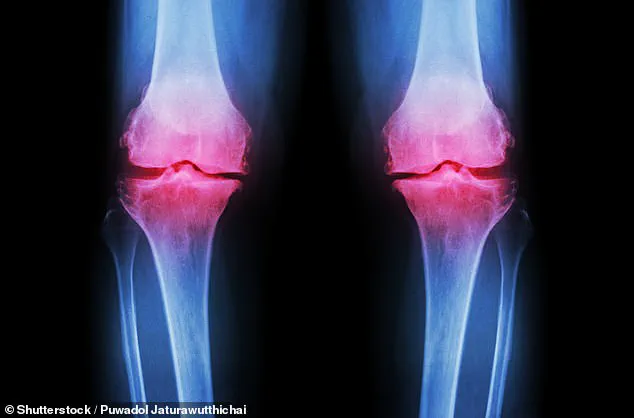

Osteoarthritis, a degenerative joint condition, develops when the protective cartilage at the ends of bones gradually breaks down over time, leading to pain, swelling and increasing difficulty moving the joint as bone begins to rub against bone.